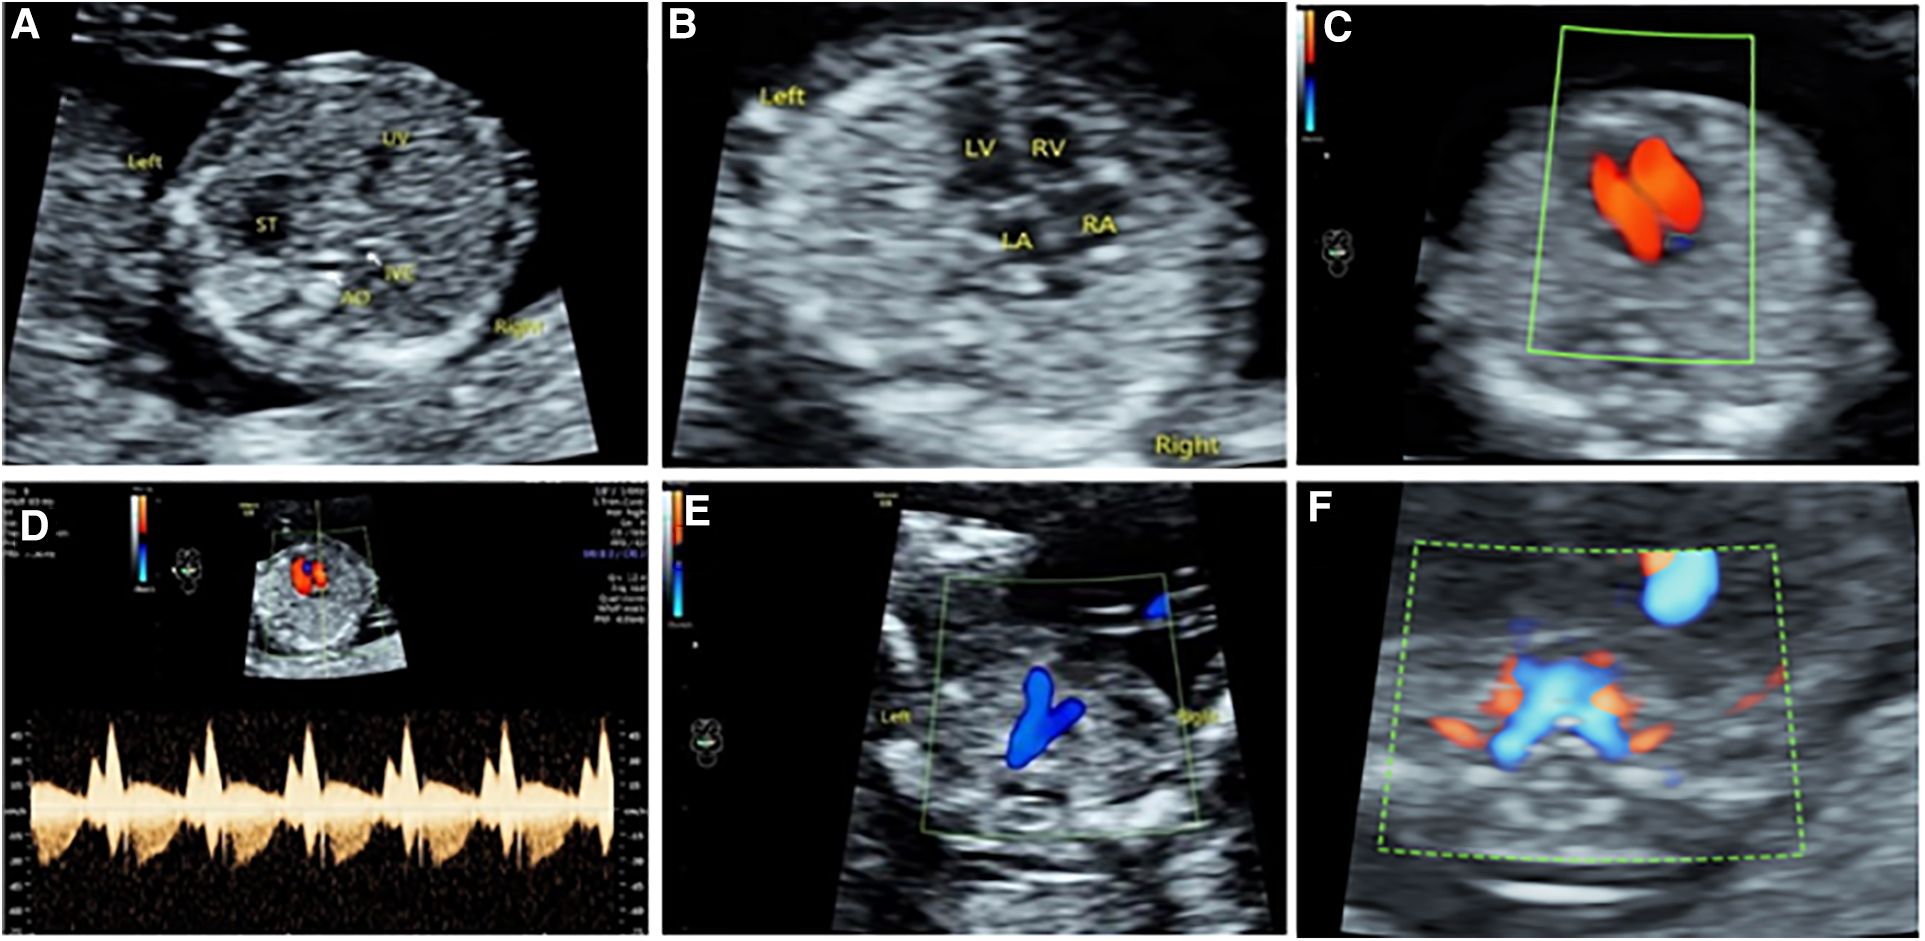

The acquisition includes upper abdominal transverse section, 4CV section, 3VT section, bilateral subclavian artery section, two-dimensional or superimposed color Doppler flowing imaging (CDFI), static blood flow, and arterial images (Figure 1). Upper abdominal transverse section: ultrasound scanning method—the acoustic beam was scanned through the gastric bubble and liver in the fetal upper abdomen, and the upper abdominal transverse section could be obtained. Observations: (1) the integrity of the abdominal wall, (2) the main structures of the upper abdominal transverse section (gastric vesicles, abdominal segment of umbilical vein, abdominal aorta, inferior vena cava), and their positions to judge the position of internal fetal organs. Four-chamber section: ultrasonic scan method—based on the examination of the upper abdominal transverse section, the probe was shifted to the head side to display the four-chamber incisal plane, and the ultrasonic beam was directed to the interventricular septum at approximately 45°. This not only ensured ventricular blood flow filling but also allowed the two-dimensional heart structure to be most clearly displayed. Observations: (1) the heart was located in the left chest cavity, and the apex of heart was facing to the left, (2) the heart cross structure, (3) combined with two-dimensional and color Doppler to observe whether the size of the heart cavity was symmetrical, and (4) whether there was tricuspid regurgitation. Three vessel–trachea section: ultrasonic scan method—based on the color Doppler ultrasound examination of the four-chamber section, the acoustic beam was tilted to the fetal head side to obtain the color Doppler vessel–trachea section. According to the actual situation, the incidence angle of acoustic beam was adjusted to achieve the optimization of the image: (1) the position relationship between the pulmonary artery and the aorta was determined, (2) the inner diameter of the pulmonary artery and the aorta were symmetrical, and (3) the ductus arteriosus and the aortic arch blood flow were normal. Bilateral subclavian artery section: ultrasound scanning method—based on the color Doppler ultrasound examination of the three vessel–trachea section, the acoustic beam continued to the fetal cephalic deflection, then the bilateral subclavian artery section was obtained, and the image was optimized by means of energy Doppler or adjusting the incidence angle of the acoustic wave. Observations: bilateral subclavian artery route.

Figure 1

Four-section approach in early pregnancy. (A) Upper abdominal transverse section. (B–D) Two-dimensional, color Doppler, and tricuspid spectrum Doppler ultrasound of 4CV section. (E) 3VT section. (F) Bilateral subclavian artery section.